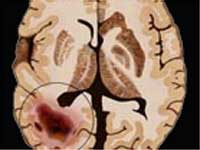

Scorpion Venom May Help Fight Brain Cancer

Researchers have found a brain-cancer therapy which uses a radioactive version of a protein found in scorpion venom. Traditional treatments like radiation and chemotherapy kill healthy cells in the process of controlling the cancer growth.

The sting of the scorpion Leiurus quinquestriatus unleashes a cocktail of neurotoxins containing a peptide that is non-toxic to humans but binds to tumour cells. In tests, the peptide has invaded tumours in breast, skin, brain and lung tissue while leaving healthy cells untouched.

In an experiment, the researchers injected this agent directly into the tumours of 59 people suffering from inoperable brain cancer. All the patients have now died, but those receiving a higher dose lived for three months longer, on average.